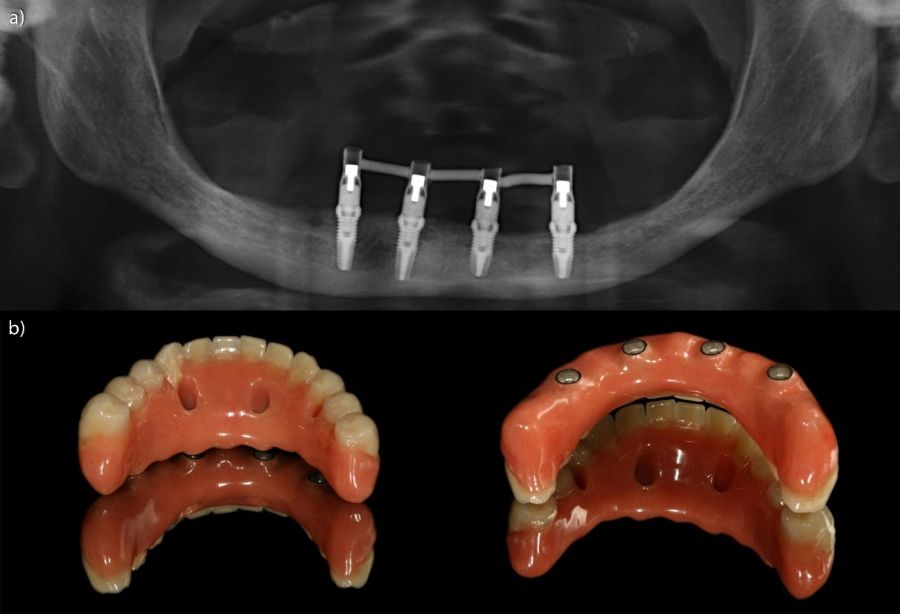

Todas las rehabilitaciones protésicas siguieron un mismo protocolo estandarizado. Una vez completada la cirugía, se procedió a la carga inmediata mediante una prótesis provisional atornillada sobre pilares transepiteliales, diseñada para distribuir las cargas de forma progresiva durante los primeros meses. Pasado un intervalo de entre seis y doce meses, y tras confirmar la estabilidad clínica y radiográfica de los implantes, se elaboró la prótesis definitiva. Esta consistió en una estructura metálica, revestida con resina acrílica, conformando una prótesis híbrida atornillada que mantenía el mismo esquema funcional que la provisional. El control radiográfico se llevó a cabo mediante radiografías panorámicas estandarizadas, realizadas siempre con el mismo sistema de posicionamiento reproducible, que incluía referencias en el suelo para los pies y apoyos simultáneos en glabela y mentón, con el fin de mantener constantes las relaciones angulares y minimizar la distorsión entre visitas. La medición de la pérdida ósea marginal se efectuó sobre la última radiografía panorámica obtenida bajo este protocolo de estandarización. Una vez digitalizada la imagen, se procedió a su calibración mediante un software específico (Digora for Windows, SOREDEX Digital Imaging Systems), utilizando como referencia una longitud conocida (el propio implante). Tras incorporar dicho valor, el programa corregía la magnificación inherente de la técnica panorámica, permitiendo realizar mediciones lineales exactas y exentas de distorsión. La pérdida ósea marginal se cuantificó en las superficies mesial y distal de cada implante, expresándose siempre como valor absoluto.

Fueron evaluadas 26 prótesis híbridas mandibulares soportadas por cuatro implantes, lo que genera un total de 104 implantes. De estas 26 prótesis, 12 fueron prótesis sobre implantes cortos (longitud < 10 mm) y 14 como prótesis sobre implantes largos (≥ 10 mm). La muestra presentó un claro predominio femenino, con 21 mujeres (80,8%) y 5 varones (19,2%). La edad media de los pacientes fue de 69,7 ± 11,2 años en el momento del inicio del estudio. A nivel de implante, la densidad media del hueso receptor fue de 866.16 ± 146.35 HU, mientras que el torque medio de inserción alcanzó 47.88 ± 9.01 Ncm. En cuanto a los diámetros de los implantes, en el grupo de los implantes cortos, el más frecuente fue el de 3,5 mm con un 56,5% de los casos, mientras que en el grupo de los implantes largos el diámetro predominante fue para 3,5 y 3,75 mm con un 32,1% para cada una de las categorías (Figura 1.a). En cuanto a la distribución de las longitudes, en el grupo de los implantes cortos, la más frecuente fue 7,5 mm con un 54,3% mientras que en los implantes largos la más frecuente fue 10 mm (47,2%) (Figura 1.b).

Todos los implantes fueron rehabilitados con prótesis híbridas atornilladas, sobre transepitelial. Este transepitelial presentó una altura entre 1 y 4 mm siendo el más frecuente 3 mm en el 75,8% de los casos. La distribución de las alturas de los transepiteliales se muestra en la Figura 2.

El análisis global de los 99 implantes reveló una pérdida ósea marginal media de 0,77 ± 0,26 mm en la superficie mesial y 0,79 ± 0,29 mm en la distal, valores que se mantuvieron dentro de los rangos considerados clínicamente aceptables para rehabilitaciones mandibulares. Cuando los implantes se categorizaron según su longitud, se observaron diferencias claras entre ambos grupos. Los implantes cortos (<10 mm) mostraron una pérdida ósea mesial media de 0,61 ± 0,23 mm y distal de 0,56 ± 0,22 mm, mientras que los implantes largos (≥10 mm) presentaron pérdidas significativamente mayores (mesial: 0,92 ± 0,19 mm; distal: 0,99 ± 0,17 mm). Dado que las pruebas de normalidad (Shapiro–Wilk) mostraron una distribución no normal en todos los grupos (p < 0,001), se aplicó la prueba no paramétrica de Mann–Whitney U. Los resultados confirmaron diferencias estadísticamente significativas tanto en la pérdida ósea mesial (U = 2068,5; p < 0,001) como en la distal (U = 2247,0; p < 0,005), indicando que los implantes cortos presentaron un comportamiento óseo más favorable que los implantes largos a lo largo del tiempo. Durante el tiempo de seguimiento que fue de media de 12,2 años (+/- 4,4; rango 6-23 años) no se objetivaron fracasos en ninguno de los implantes por lo que la supervivencia acumulada fue del 100%. El análisis del periodo de seguimiento mostró diferencias claras entre ambos grupos. Los implantes largos (≥10 mm) presentaron un tiempo medio de función de 14,1 ± 4,2 años (rango: 9–23 años), mientras que los implantes cortos (<10 mm) registraron un seguimiento significativamente menor, con una media de 9,8 ± 2,7 años (rango: 6–15 años). En las Figuras 3- 10 se muestran dos casos incluidos en el estudio, uno de cada situación descrita.